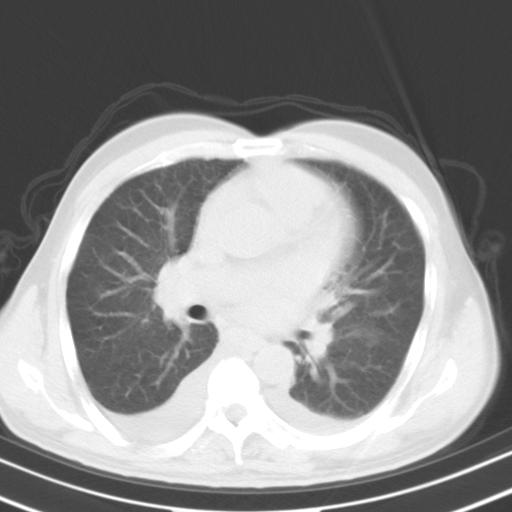

以下是引用zjzjr在2010-3-21 17:39:00的发言:[br]右下中心型肺癌并阻塞性肺炎/不张,纵膈淋巴结肿大,右侧大量胸腔积液,左侧少量胸腔积液

以下是引用zxl51642在2010-3-21 17:06:00的发言:[br]右下中心型肺癌并阻塞性肺炎/不张,纵膈淋巴结肿大,右侧大量胸腔积液,左侧少量胸腔积液,少量腹水。建议纤维支气管镜进一步检查。